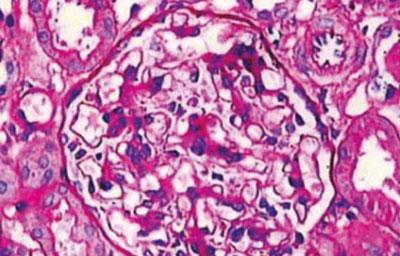

- гломерулонефрит, выраженная недостаточность почек;